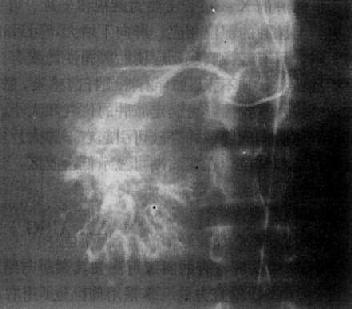

选择性肝动脉影是诊断肝癌的有效方法,它能查出直径小至2cm的肝癌,并确定其范围与数目,供血是否丰富,还可了解有无肝硬化和附近有无肿瘤转移。肝癌的动脉造影可有以下表现:①显示肿瘤血管,表现为肿瘤区内大小不均、形状不规则的血管影或呈“湖样”充盈,其供血动脉增粗;②动脉拉直和移位,动脉边缘不规则且僵硬,系因肿瘤包绕所致;③毛细血管期可见肿瘤染色,呈高密度的结节影;④肝实质期显示为充盈缺损区;⑤有时可形成动静脉瘘,使相邻的门静脉分支早期显影(图4-3-1)。

原发性肝癌动脉造影

图4-3-1 原发性肝癌动脉造影

肝动脉造影显示肝内一团巨块状肿瘤血管,大小不均,形态不规则,

其中心呈湖样充盈。供血动脉增粗、迂曲